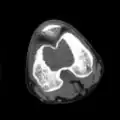

A variety of imaging studies can be used to diagnose chondroblastoma, with radiographs being the most common.[10][8] Laboratory studies are not considered useful.[14] Classical chondroblastoma (appearing on long bones) appears as a well-defined eccentric oval or round lytic lesion that usually involves the adjacent bone cortex without periosteal reaction.[10][13] A sclerotic margin can be seen in some cases.[10][13] For long bone chondroblastomas the tumor is typically contained to the epiphysis or apophysis but may extend through the epiphyseal plate.[10][13] Chondroblastomas are usually located in the medullary portion of bones and can, in some cases, include the metaphysis.[10][13] However, true metaphyseal chondroblastomas are rare and are typically the result of an extension from a neighboring epiphyseal legion.[10][13] Most lesions are less than 4 cm.[10] A mottled appearance on the radiograph is not atypical and indicates areas of calcification which is commonly associated with skeletally immature patients.[10] Additionally, one-third of all cases involve aneurysmal bone cysts which are thought to be the result of stress, trauma or hemorrhage.[10] In cases involving older patients or flat bones, typical radiographic presentation is not as common and may mimic aggressive processes.[10][13]

Other imaging techniques involve computed tomography (CT), magnetic resonance imaging (MRI), and bone scans, which may be helpful in determining the anatomical boundaries, associated edema, or biological activity of the chondroblastoma, respectively.[8][10] MRI studies may show extensive oedema around the lesion and show variable T2 signal intensity.[15]

1. b. CT scan shows chondroblastoma of thigh bone near knee more clearly -

1. c. CT scan of chondroblastoma of thigh bone near knee (cross-section view) -